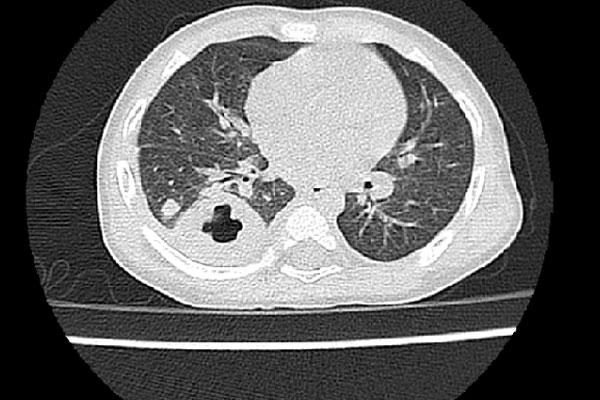

Bé gái bị áp-xe tuyến mang tai trái nghi do nhiễm vi khuẩn Burkholderia pseudomallei gây nên bệnh Whitmore. Ảnh: D.T.